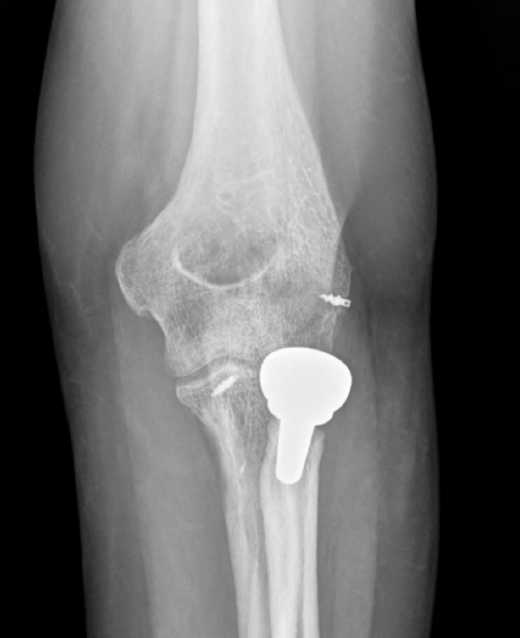

- Tipo I. Las fracturas de la punta de la coronoides son pequeñas y por lo general no son sintetizables. Usaremos un pasador de sutura para llevar una lazada desde el fragmento hasta la cortical posterior del cúbito a través de 2 orificios perforados con broca o bien reinsertaremos la cápsula mediante un arpón(9). Además habrá que tratar el resto de las lesiones cuando se vean involucradas: síntesis o reemplazo de la cabeza del radio, y reinserción o reparación del LCL(10). Si persiste la inestabilidad tendremos que revisar el LCM (Figura 4). Algunos autores han señalado buenos resultados con la reparación o reemplazo de la cabeza radial y reparación del LCL sin fijar la coronoides(11).

- Tipo II. Las fracturas de la faceta AM se tratan mejor con una placa de soporte y la reinserción del LCL (Figura 5). Si el tamaño lo permite, también podemos usar tornillos canulados parcialmente roscados. En algunos casos será suficiente con la reparación del LCL, siempre y cuando tengamos una reducción concéntrica en la radiografía sagital.